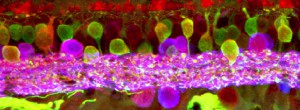

Translational research in regenerative stem cell therapies for retinal degenerative diseases: from the swine animal model of retinal atrophy to clinical trials in human patients with age-related macular degeneration, retinitis pigmentosa and Stargardt’s disease